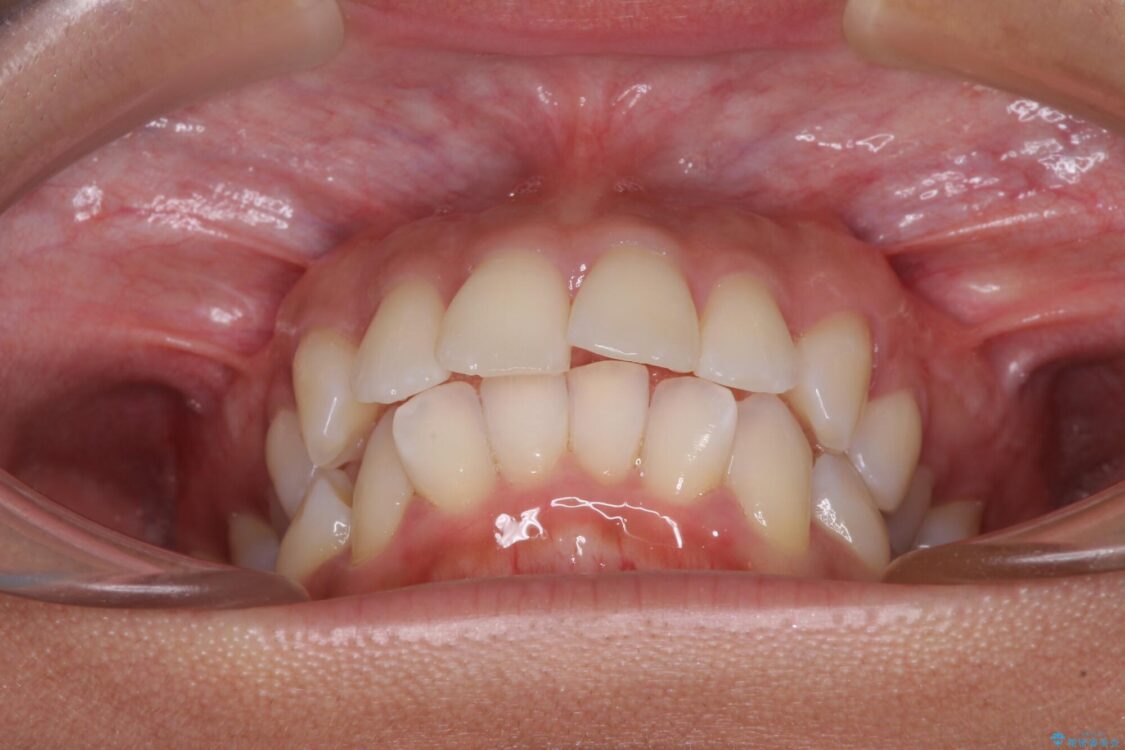

治療前

• 抜歯矯正で唇を閉じやすく 目立たないワイヤー装置 治療前画像